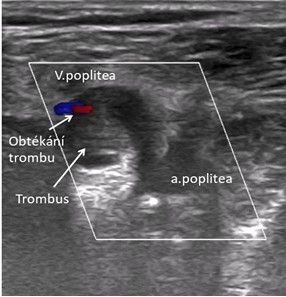

Pacient byl po vyšetření internistou indikován k léčbě apixabanem podávaným týden v dávce 2× 10 g a poté k pokračovací dávce 2× 5 mg. Léčba byla zahájena 27. července, otok vznikl 2. července. Po asi 14 dnech léčby částečně ustoupil, ale pokud pacient nenosí elastickou bandáž, vznikne otok kolem kotníku. Při kontrole v naší ambulanci po 14 dnech léčby má pacient malý otok kolem pravého kotníku. Ostatní všechna známá fyzikální vyšetření zaměřená na hlubokou trombózu jsou negativní, ale sonograficky je stále patrný částečně obturující, spíše hyperechogenní trombus v popliteální žíle, se známkami obtékání, kompresibilním tlakem sondy na 30 % průsvitu žíly (obr. 1a, b). Echokardiografie bez známek plicní hypertenze. Pokračováno v léčbě apixabanem v dávce 5 mg 2× denně, kontrolní laboratorní vyšetření doložila normální renální funkce.

Obr. 1a Duplexní ultrazvukové vyšetření – podkolenní jamka; příčný řez přes v. poplitea s neobturujícím trombem, nemohogenní, hypoechogenní – „staršího data“.